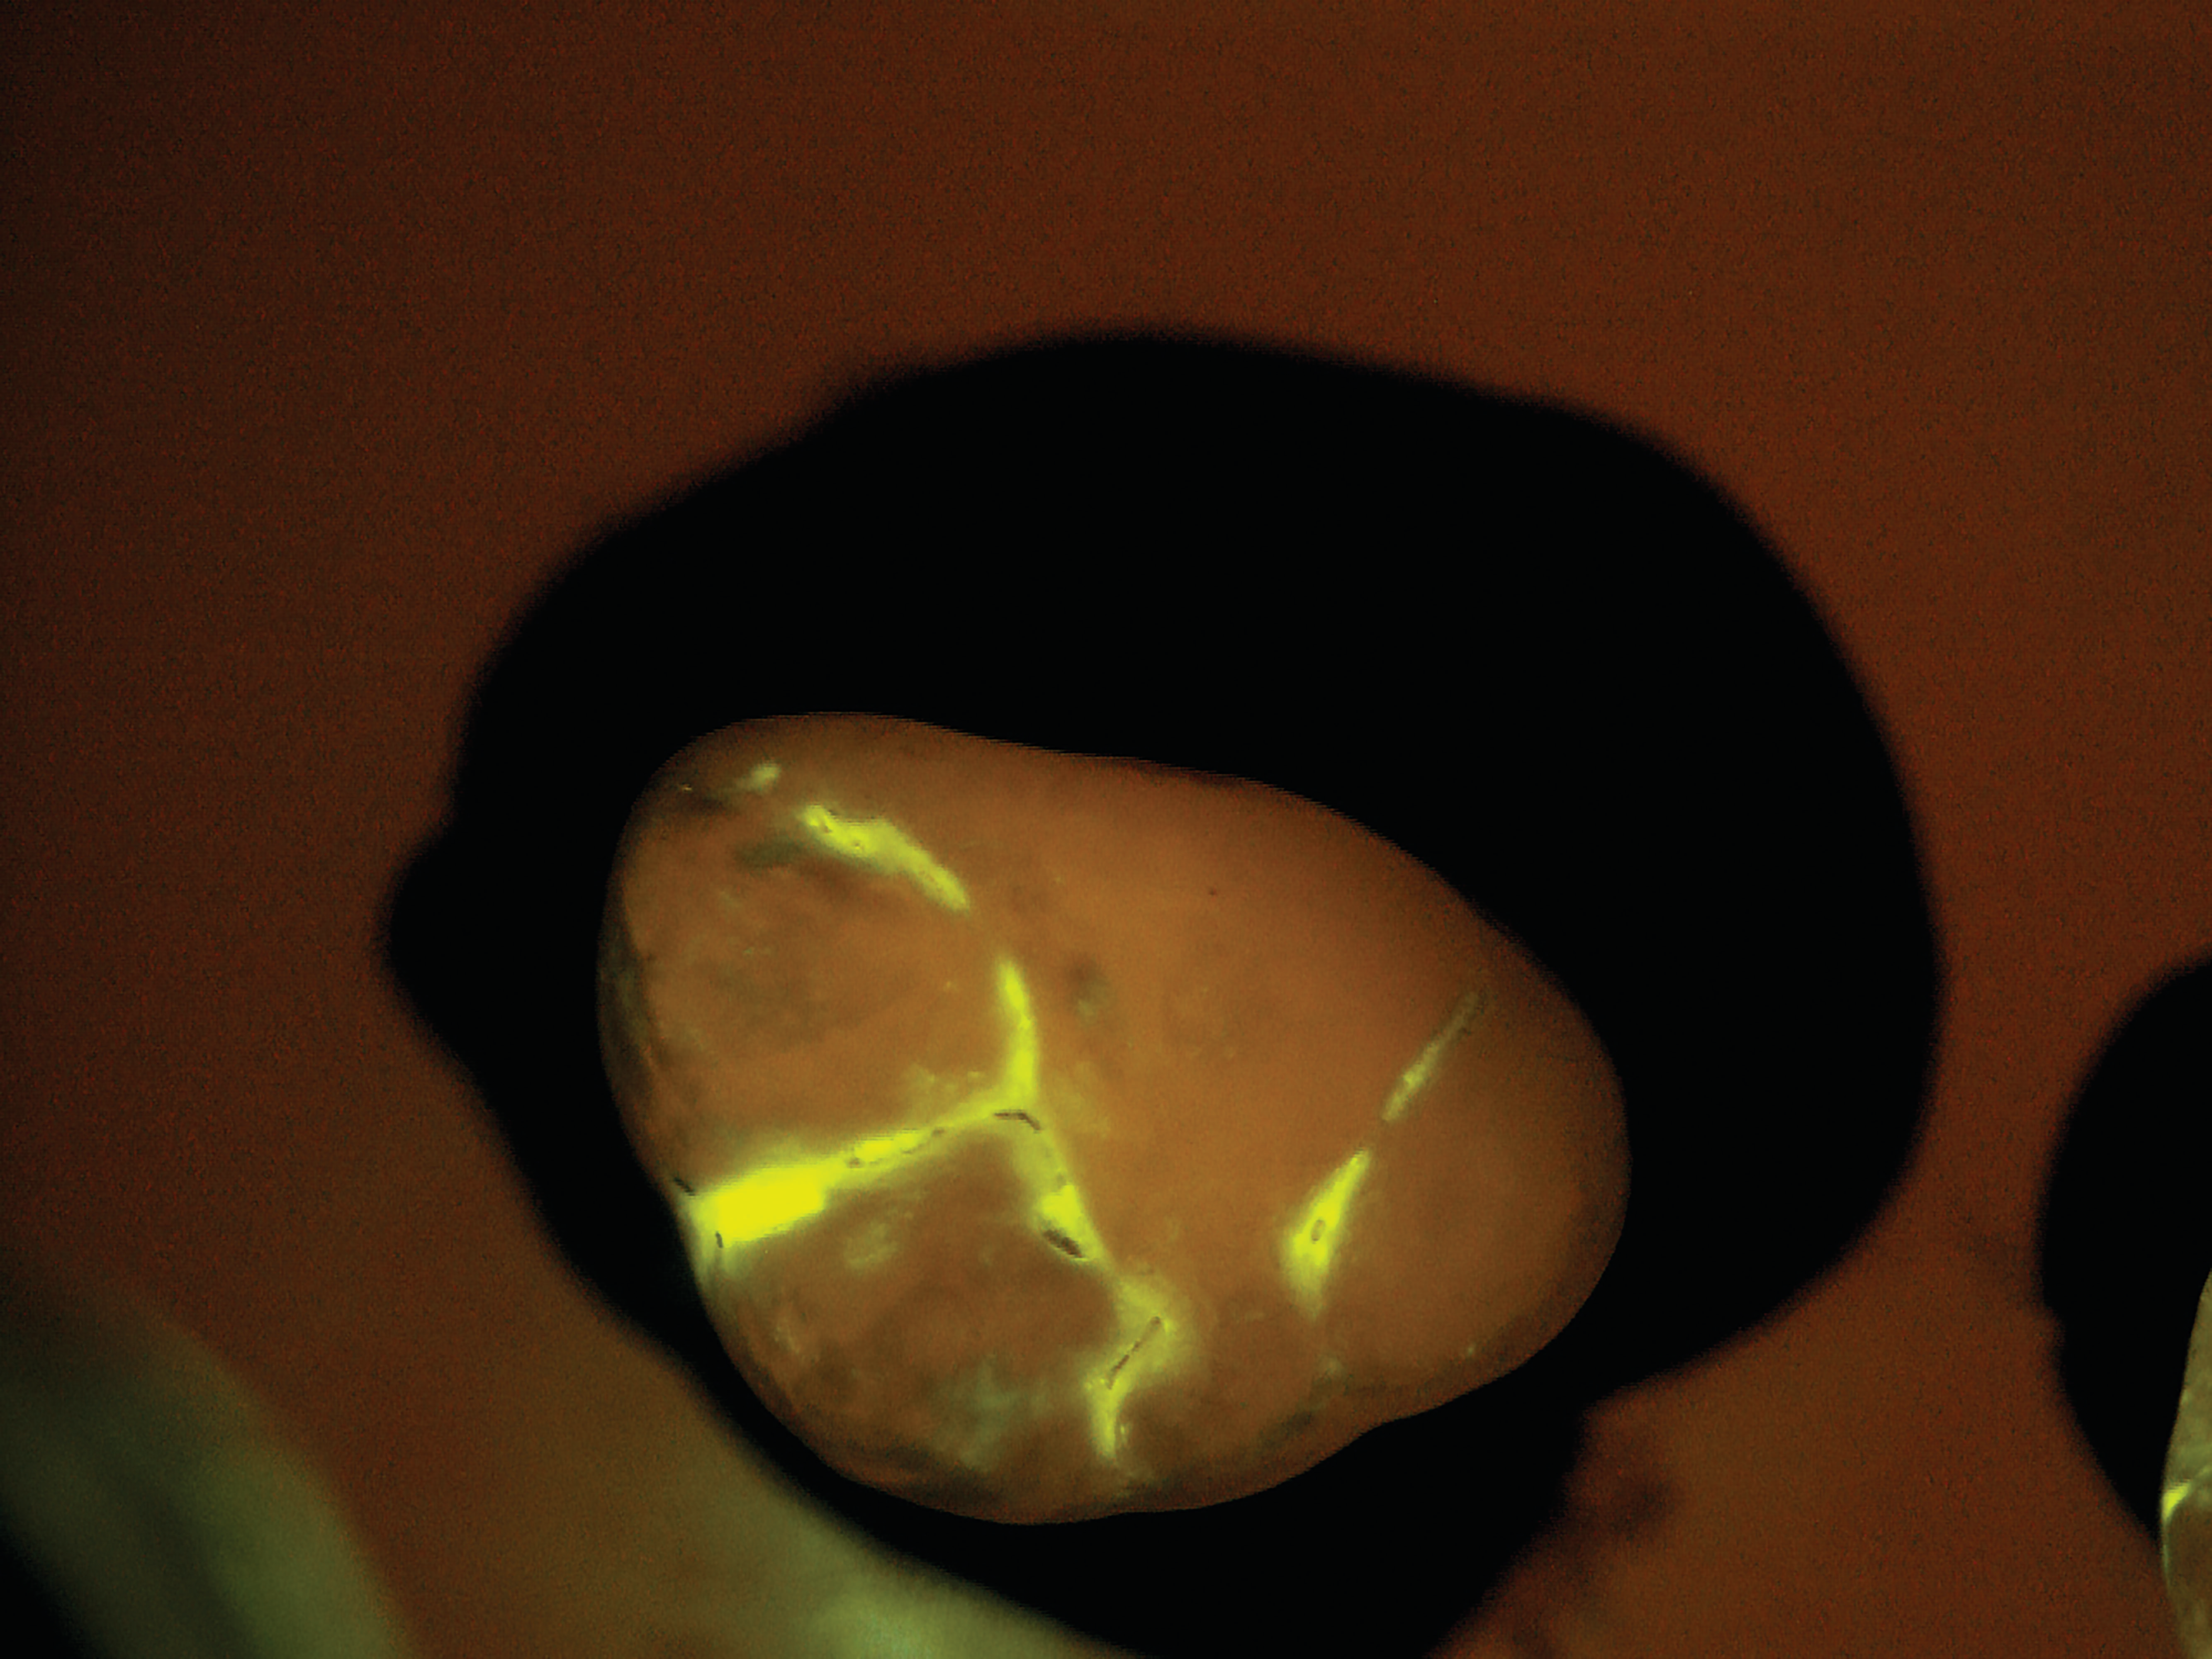

SB: The practice would administer the diagnostic test as part of a routine prophy exam. We have developed a mouth rinse where the targeted starch particles are dispersed at a low concentration in water. The patient rinses first with the diagnostic solution and then with plain water. All that remains after the water rinse are the particles that have penetrated

the tiny porosities in the enamel and attached themselves temporarily to the active subsurface lesions. The particles contain molecules that fluoresce or light up under exposure from a standard blue curing light. Within seconds, the dentist receives a direct visual diagnosis because the illuminated areas indicate areas of porosity.

After the patient drinks the mouth rinse containing the targeted starch particles and then rinses with water, particles adhering to enamel porosities fluoresce under a standard blue curing light.